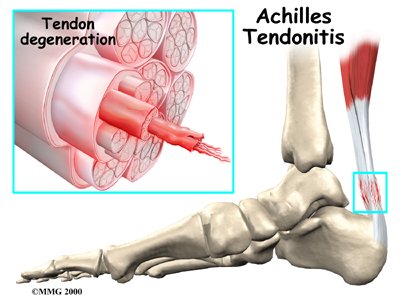

Tendon injuries can show up anywhere in your body. Doctors see tendonitis most often in certain sites.

Achilles Tendonitis

Achilles Tendon

found in the lower leg. Damaged Achilles tendons carry a higher risk of rupturing because of the weight they bear while standing and walking.

Related Document: *client_company's Guide to Achilles Tendon Problems

Aging seems to cause tendon damage in some cases. As we age, the tissues of the tendon can break down, or degenerate. Age-related tendon problems do not seem to cause inflammation. The tendon material itself is more affected in these conditions and some surgeon's refer to this type of tendon problem as tendonosis.

Some researchers think that a decreased blood supply to the tendons can cause the tendon damage in tendonosis. The decreased blood supply does not allow the tendon to get enough oxygen from the blood. This leads to a condition where the tendon degenerates. The collagen material that makes up the tendon actually becomes weaker and loses its nylon rope appearance. This type of degeneration has been noted in the rotator cuff around the shoulder, in the Achilles tendon in the heel and in the tendons of the elbow.